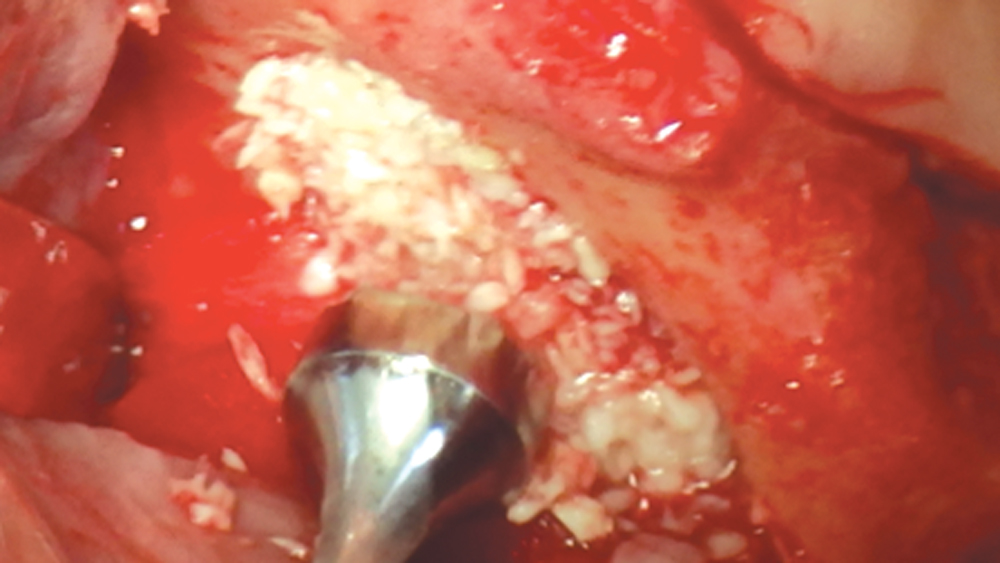

Bone graft putty is shown inserted into an osteotomy via osteotome sinus graft technique

Newport Biologics Bone Graft Putty Mineral-Collagen Composite is a calcium phosphate-based grafting material that becomes moldable upon hydration. It features a carbonate apatite structure similar to natural bone, combined with a type I collagen derived from bovine Achilles tendon. The mineral particles are dispersed within collagen fibers, forming a 3D matrix that is fully resorbed during the natural process of bone formation and remodeling. This bone graft putty is ideal for sites that require no movement of the graft material, such as areas of high muscle pulls or sinus augmentation procedures. Shown is bone putty inserted into an osteotomy via the osteotome sinus graft technique.